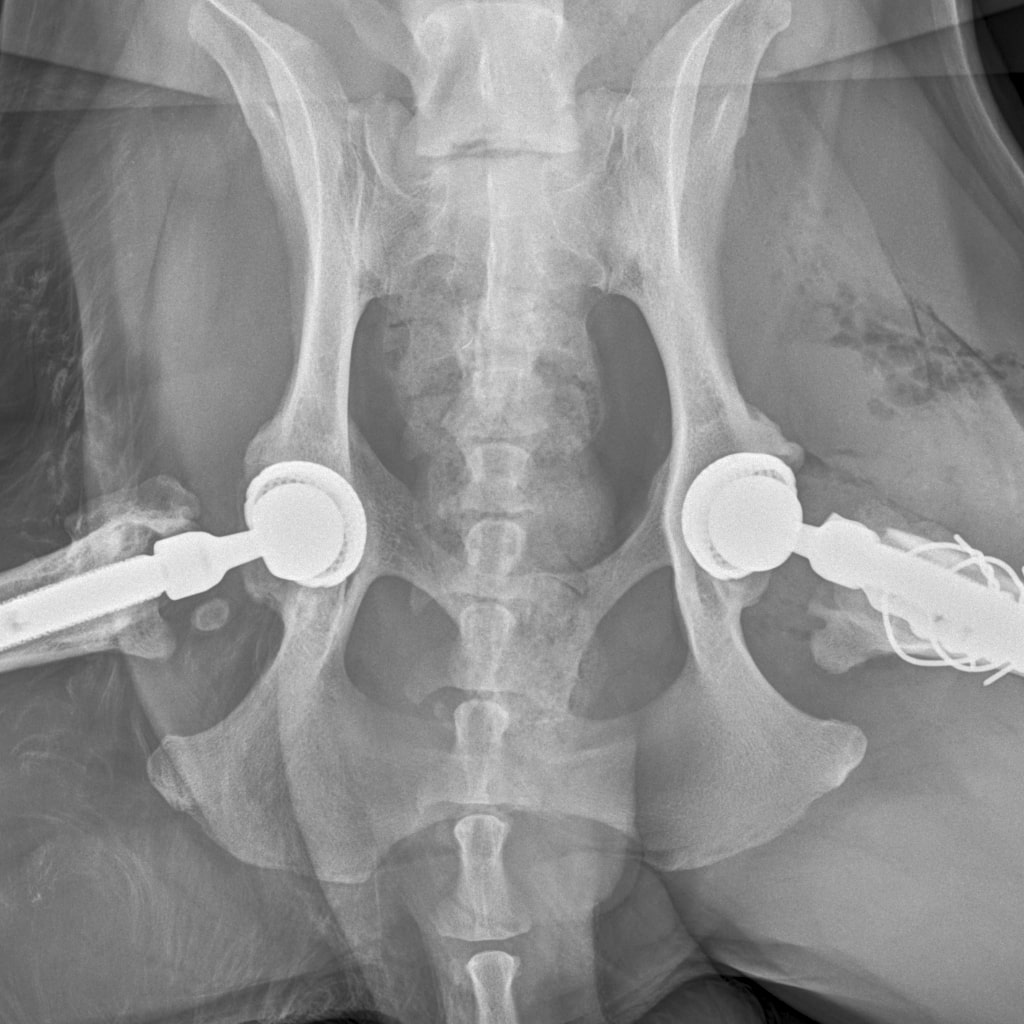

8A836050-66CA-42B2-94D3-F13B288A592B.jpeg

39B2671E-39B9-4502-9E11-ADB169612F24.jpeg

6950B9C9-79EA-4F34-A780-9C3C6BA31B49.jpeg

58C20B18-AA4E-4386-BF83-56CE5E282844.jpeg

Наш металлический мальчик

Железный дровосек